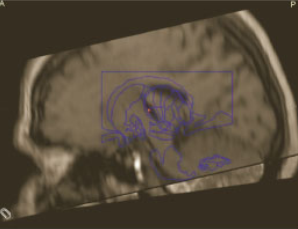

Coordinates for Voa were, according to Guiot scheme,27 0.5mm posterior to the mid-commissure point (MCP) in order to reach the posterior part of Voa and anterior part of Vop, 10mm lateral and at the level of the anterior commissure-posterior commissure (AC-PC) plane (Figure 3). Only indirect visualization was possible as conventional MRI sequences cannot delineate different thalamic nuclei.

Figure 3 Guiot Scheme, 10mm from midline AC-PC showing the Voa, Vop and Vim.